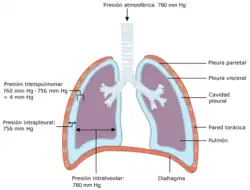

Los pulmones están situados dentro del tórax y a ambos lados del corazón. Están protegidos por las costillas y separados el uno del otro por el mediastino. Están cubiertos por una doble membrana llamada pleura, entre ambas pleuras se forma una cavidad (cavidad pleural) que está ocupada por una fina lámina de líquido seroso.

Pleura

La pleura es una membrana de tejido conjuntivo, elástica, que evita que los pulmones rocen directamente con la pared interna de la caja torácica. Posee 2 capas, la pleura parietal o externa que recubre y se adhiere al diafragma y a la parte interior de la caja torácica, y la pleura visceral que recubre el exterior de los pulmones, introduciéndose en sus lóbulos a través de las cisuras. Entre ambas capas existe una pequeña cantidad (unos 15 cm³) de líquido lubricante denominado líquido pleural.

Ventilación pulmonar

La ventilación es el proceso por el cual el aire atmosférico rico en oxígeno entra en los pulmones, los cuales expulsan a continuación aire pobre en oxígeno y rico en dióxido de carbono. Consta de 2 fases, la inspiración y la espiración:

- La inspiración tiene lugar cuando la contracción del diafragma y los músculos intercostales externos aumentan el volumen de la cavidad torácica y hacen que el pulmón se expanda. La presión intraalveolar se hace negativa con respecto a la atmosférica y entra aire al pulmón hasta que desaparece el gradiente de presión.[7]

- La espiración ocurre cuando el diafragma se relaja y la cúpula diafragmática sube pasivamente por su elasticidad, la presión intrapulmonar se hace positiva con respecto a la atmosférica, el pulmón disminuye su volumen y el aire sale al exterior hasta que desaparece el gradiente de presión y la presión intraalveolar se iguala a la atmosférica.[7]

En estado de reposo el volumen de aire que entra en el pulmón durante una inspiración se llama volumen corriente y es 500 cm³, la frecuencia respiratoria es de 12 ciclos por minuto. La capacidad pulmonar total oscila entre 4000 y 6000 cm³, dependiendo de la edad, peso y sexo; siendo más elevada en los hombres que en las mujeres.[8]